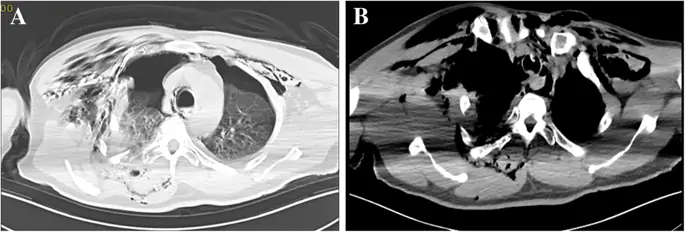

Письменное информированное согласие на публикацию данного дела было получено от пациента. Мужчина 56 лет (рост 165 см; вес 70 кг) без значительного медицинского анамнеза обратился в отделение неотложной помощи с жалобами на боль в правой груди, застой в груди и одышку после получения тупой травмы правой груди. Его жизненные показатели были следующими: частота сердечных сокращений (ЧСС), 91 уд / мин; частота дыхания (ОР), 34 вдоха / мин; артериальное давление (АД), 108/71 мм рт.ст.; и начальная пульсовая оксиметрия насыщения (SpO 2) 85%. Газ артериальной крови: рН 7, 35, ПаСО 2 47 мм рт. Ст. И ПаО 2 49 мм рт. Хрипящая грудь и парадоксальное дыхание были очевидны. Значительная подкожная эмфизема в области шеи и передней части груди была диагностирована с выраженным крепитацией. Компьютерная томография (КТ) показала массивную подкожную эмфизему, пневмомедиастинум, множественные переломы ребер, двусторонний гемопневмоторакс и компрессионный пневмоторакс (рис. 1 а и б). Было замечено смещение сочленения грудины, и стернальная часть правого первого ребра проникла через заднюю стенку трахеи над килем (рис. 2). Грудная трубка была вставлена для декомпрессии пневмотораксов и гемопневмоторакса, и проблемы с дыханием были облегчены. К сожалению, быстрое ухудшение подкожной эмфиземы указывало на постоянную утечку воздуха через разрыв через 3 часа. У пациента развился респираторный дистресс и он стал гемодинамически нестабильным. Эмерджентная КТ показала, что правое первое ребро проникло через заднюю стенку трахеи примерно на 6 см ниже голосовой щели и на 6 см выше киля (рис. 3а). Первое ребро разделило трахею на две части: 5, 3 мм в диаметре слева и 6, 6 мм справа (рис. 3, б и в). Пациент был быстро переведен в операционную. Он был взволнован, при дыхательной недостаточности и его жизненные показатели были: ЧСС 108 уд / мин; 30 вдохов в минуту; BP 90/58 мм рт.ст. и SpO 2 80%. Мы поддерживали гемодинамическую стабильность с помощью внутривенного фенилэфрина. Фиброоптический бронхоскоп был сразу же доступен с эндотрахеальными трубками разных размеров. Общая анестезия была индуцирована мидазоламом 2 мг, фентанилом 0, 05 мг и 2% ~ 5% севофлюраном при сохранении спонтанной вентиляции. Стерильный гибкий волоконно-оптический бронхоскоп, загруженный 5, 5 мм эндотрахеальной трубкой (наружный диаметр 7, 3 мм), идентифицировал разрыв трахеи, и эндотрахеальная трубка была продвинута дистально мимо места разрыва. Он самопроизвольно дышал с фракцией вдыхаемого кислорода 100%, дыхательным объемом 330 мл, частотой 30, SpO 2 95% и парциальным давлением конечного прилива двуокиси углерода (PetCO 2) 40 мм рт. Глубина анестезии поддерживалась до достижения показателя биспектрального индекса 40-60. Хирургическая бригада открыла грудную полость, чтобы обнажить правое первое ребро, а правое первое ребро было удалено примерно через 30 минут (рис. 4а). Эндотрахеальную трубку диаметром 7, 5 мм затем заменяли и располагали дистально до разрыва под руководством гибкой бронхоскопии. После подтверждения расположения эндотрахеальной трубки внутривенно вводили цисатракурий 14 мг и фентанил 0, 15 мг. Пациенту была проведена искусственная вентиляция легких с интервалом положительной вентиляции. Респираторные параметры были следующими: фракция вдыхаемого кислорода 60%, дыхательный объем 550 мл, частота 12, пиковое давление в дыхательных путях 22 см H 2 O, SpO 2 98% и PetCO 2 38 мм рт. Непосредственное хирургическое восстановление разрыва трахеи было успешным, и он был переведен в отделение интенсивной терапии. В отделении интенсивной терапии ему управляли на вентиляторе с синхронизированной прерывистой принудительной вентиляцией и постоянным положительным давлением в дыхательных путях. Для улучшения легочной функции на 5-й день после первой операции были выполнены плановые хирургические операции по восстановлению перелома грудины, множественных переломов ребер и гемопневмоторакса под общей анестезией, а у пациента был экстубирован на 7-й день после операции. Повторная КТ продемонстрировала целостность стенки трахеи (рис. 4 б). Комплексная реабилитация проводилась в течение 2 недель, и он был выписан домой в послеоперационный день 41.

фигура 2

КТ с использованием многослойной техники, показывающая разрыв трахеи, вторичный по отношению к вывиху правого первого ребра. Сагиттальное КТ изображение грудной клетки. b Осевое КТ изображение грудной клетки. (C) Объем рендеринга грудной клетки

Изображение в полном размере